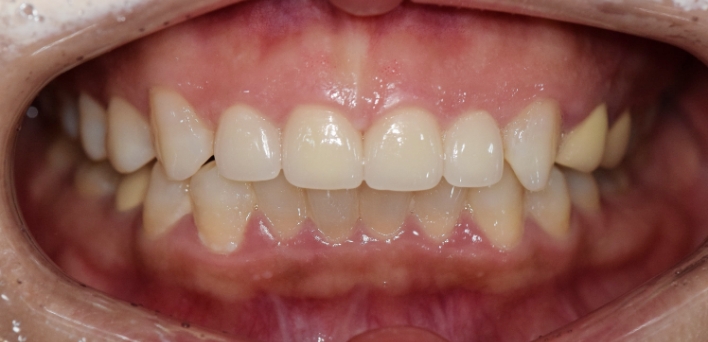

단순하게 예쁘고, 심미적으로 만드는 인위적인 작업물이 아닌,

자연치아와 가장 유사하도록 치아를 복구하는데에 초점을 맞추어

치아복구 + 치아성형 2가지의 장점을 합쳐

개개인 손상 정도에 따른 맞춤형 보철을 제작합니다.

그저 예쁘기만한 부자연스러운 라미네이트가 아닙니다.

더서울치과의원은 각 개인의 얼굴 특성에 맞는 맞춤형 라미네이트를 선물합니다.